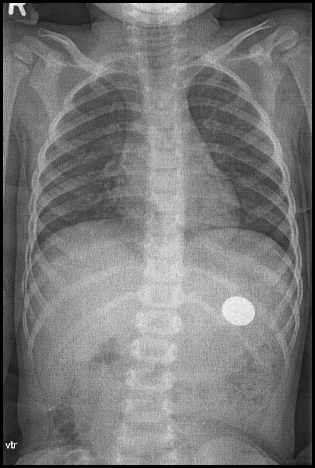

No, my little boy... I'm sure I left that coin here!

Do you know where it is...?

Easy! In The Netherlands one is not allowed to take medical X-ray pictures home, so be sure you have your normal digicam with you and take a picture of the screen in the doctors office. At home edit the picture by cutting away all around the original... Then add the black line.

The picture is part of my son's 'My Life in Pictures' series Smile

About the coin...

It was a € 2.- piece, the biggest there is. The doctor explained: "When it fits up here, it will fit down there too..." Anyway, although we 'searched', we never found it again. Well, we reduced his weekly allowance a bit Wink

Yes, he told me he swallowed it. I can tell if he's joking or not. The picture proofed he did.

Well, there was a second X-ray in which no coin was present, so it was thrown out or digested, who knows? Wink